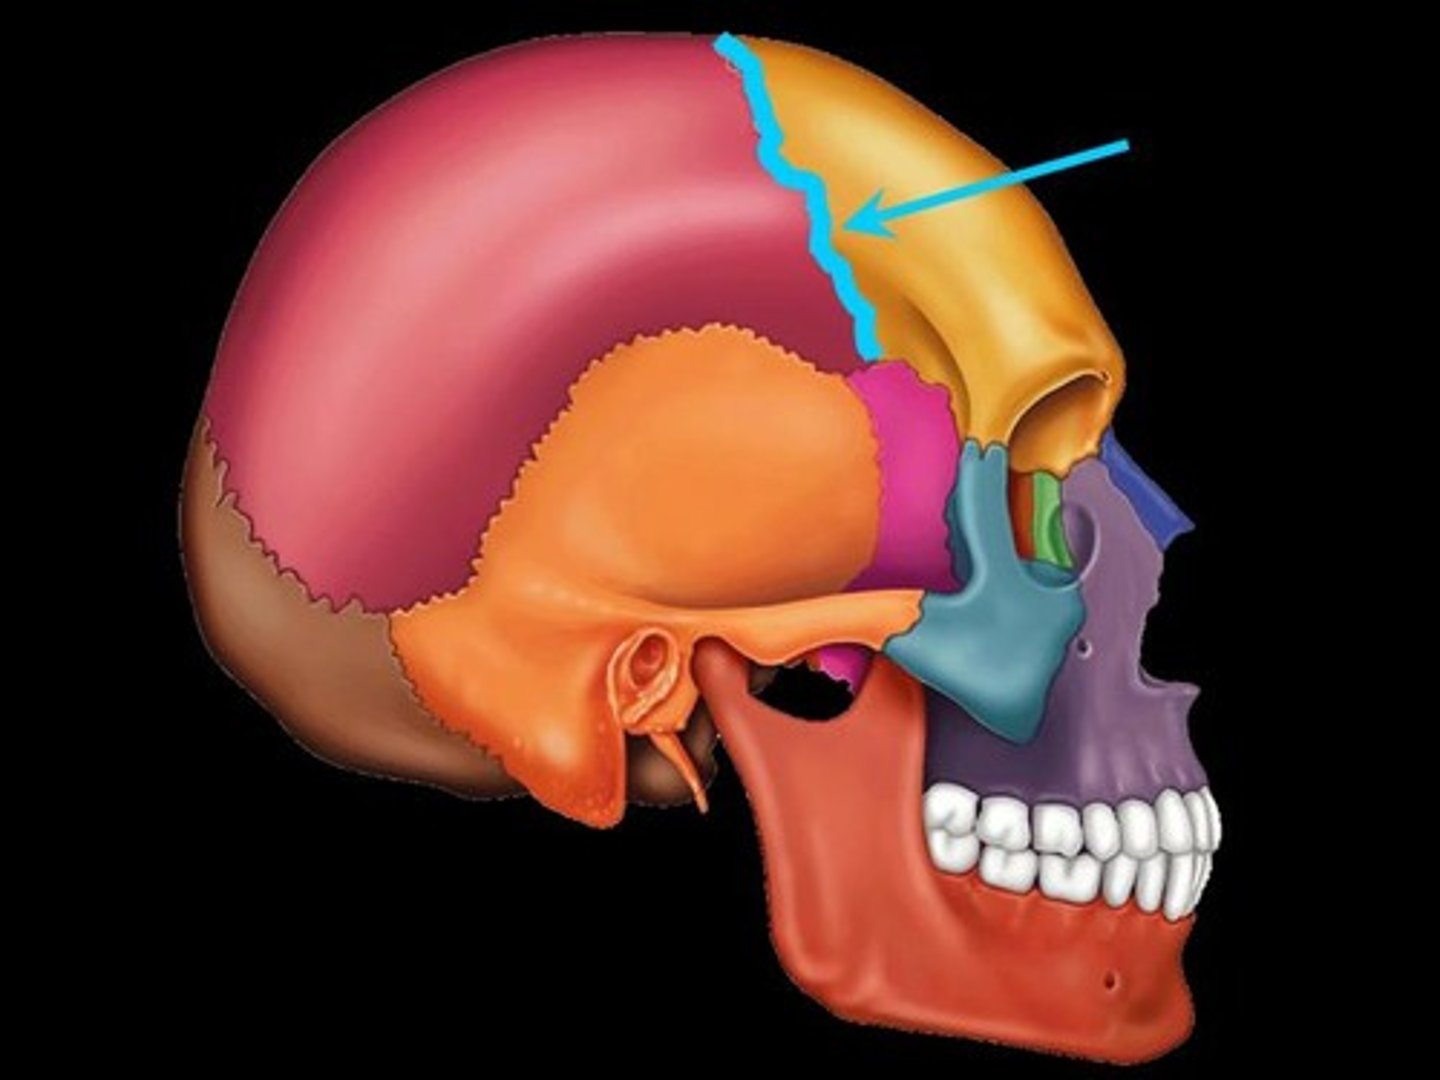

coronal suture

the suture between the parietal and frontal bones of the skull

pterion

Junction of frontal, parietal, sphenoid, and temporal bones. Structural vulnerability as it is thin and middle meningeal artery is just deep, so hard head blow can result in subdural hematoma